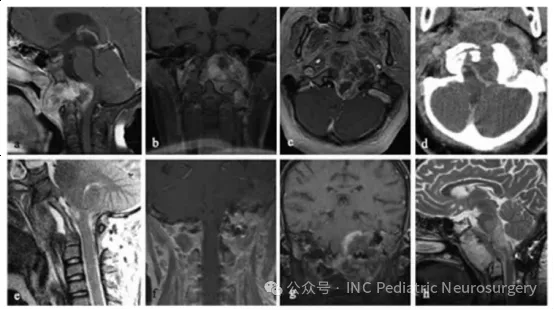

患者于2003年就诊,11岁。主诉为下位颅神经功能缺损持续2个月,伴有鼻塞、斜颈(torticollis)以及右足阵挛(clonus)。影像学显示斜坡区巨大破坏性肿块,向左侧延伸,侵犯鼻咽部,并包绕左侧颈内动脉(图4)。患者在经口活检后,接受经口、经腭、经下颌联合入路的部分肿瘤切除术,手术历时13小时,术后行枕骨-C3内固定融合术。病理结果显示为经典型脊索瘤,伴软骨样分化区域,MIB-1增殖指数30-50%,并检测到p53蛋白表达。

尽管接受了光子放疗,患者在诊断10个月后出现肿瘤进展。复发后接受5个月的Trabectedin(抗肿瘤化疗药物)治疗,但病情仍迅速恶化,患者最终于诊断后15个月去世。

图4. 患者5巨大斜坡脊索瘤伴脑干受压

(a)术前矢状位T1加权增强MRI;

(b)术前冠状位T1加权增强MRI;

(c)术前轴位T1加权增强MRI;

(d)术前轴位CT扫描;

(e)术后矢状位T1加权增强MRI;

(f)术后冠状位T1加权增强MRI;

(g)术后1年冠状位T1加权增强MRI;

(h)术后1年矢状位T2加权MRI。